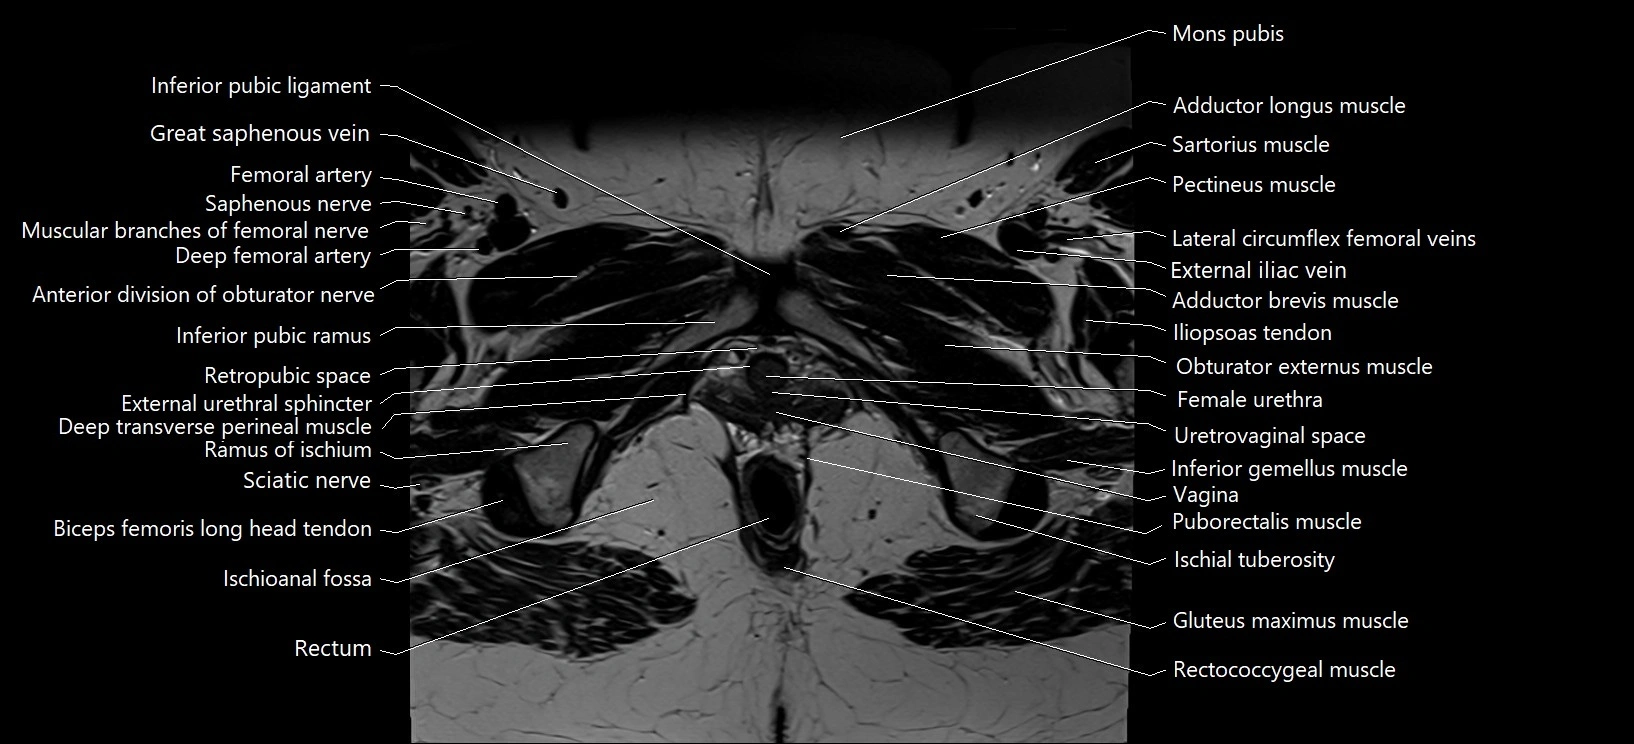

- Adductor brevis muscle

- Adductor longus muscle

- Anterior division of obturator nerve (Anterior branch of obturator nerve)

- Deep femoral artery (profunda femoris)

- Deep transverse perineal muscle

- External urethral sphincter (female)

- Female urethra

- Gracilis muscle

- Inferior gemellus muscle

- Inferior pubic ligament

- Inferior pubic ramus

- Ischioanal fossa

- Lateral circumflex femoral veins

- Mons pubis

- Muscular branches of femoral nerve

- Obturator externus muscle

- Pectineus muscle

- Puborectalis muscle

- Ramus of ischium

- Rectum

- Retropubic space

- Saphenous nerve

- Sciatic nerve

- Urethrovaginal space

- Vagina

- great saphenous vein